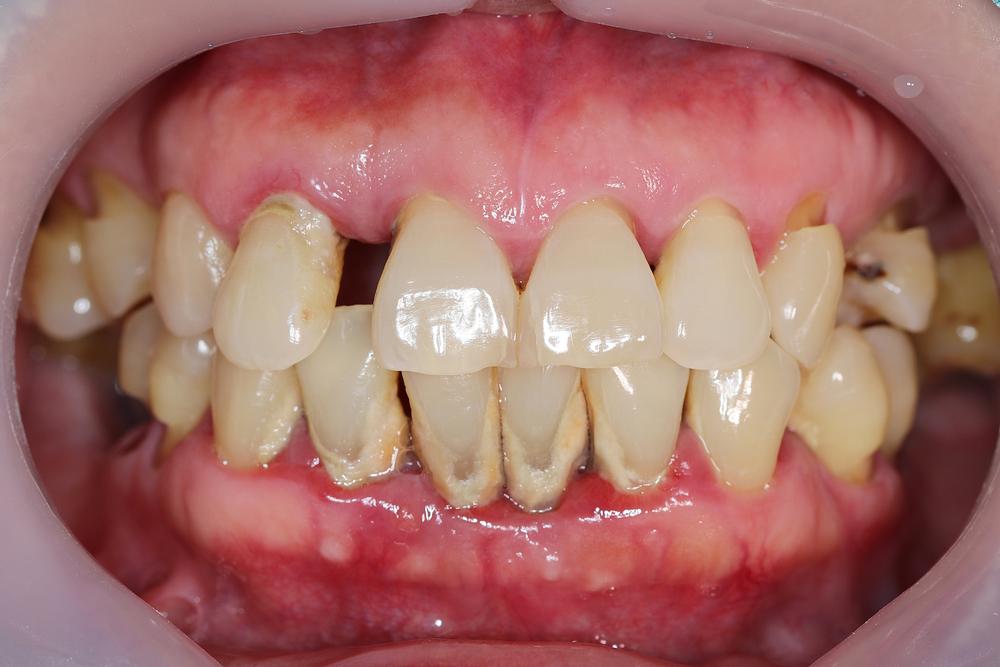

Gejala khas trench mouth yaitu adanya gusi yang meradang parah disertai jaringan mati yang berbentuk kawah. Jaringan tersebut biasanya tertutup selaput berwarna keabuan.

- Gusi bengkak atau memerah.

- Muncul ulkus (luka) di antara gigi dan gusi.